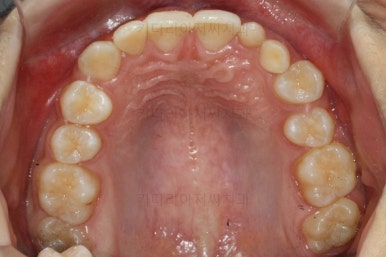

마찬가지로 부산교정치과 키다리아저씨치과에 처음 내원하셨을 당시의 입안 모습입니다.

화살표로 표시된 치아가 작은 앞니 부분인데 크기가 매우 작고 뾰족한 것을 볼 수 있어요. 유치가 아니고 평생 써야 하는 영구치입니다. 이러한 상태를 "왜소치"라고 표현하는데, 치아 크기의 문제로 여러 가지 문제점이 생길 수 있어요.

또 다른 문제는 위아래 앞니가 매우 많이 겹쳐져 있어서 아래 앞니가 거의 보이지 않는다는 점입니다.

그 다음 문제는 왼쪽 송곳니 부분(붉은색 동그라미)이 유치가 남아있고, 영구치가 매복되어 있는 경우였어요.

화살표를 보시면 송곳니가 나오지 못하고 뼈속에 묻혀 있는 것을 볼 수 있습니다.

상태를 보면 옆에 있는 안그래도 작은 왜소치의 뿌리를 건드리는 양상으로 있어서 좀 더 정밀한 3차원 CT를 찍어 보기로 했습니다.